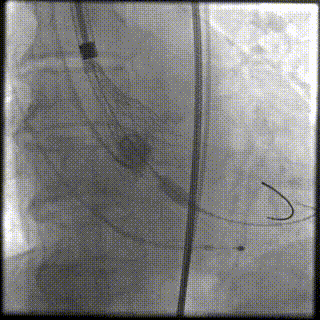

主动脉根部造影

22mm球囊预扩

输送器顺利过弓跨瓣

瓣环零位定位释放

第一次释放到工作位

工作位造影位置偏深

完全回收再次定位